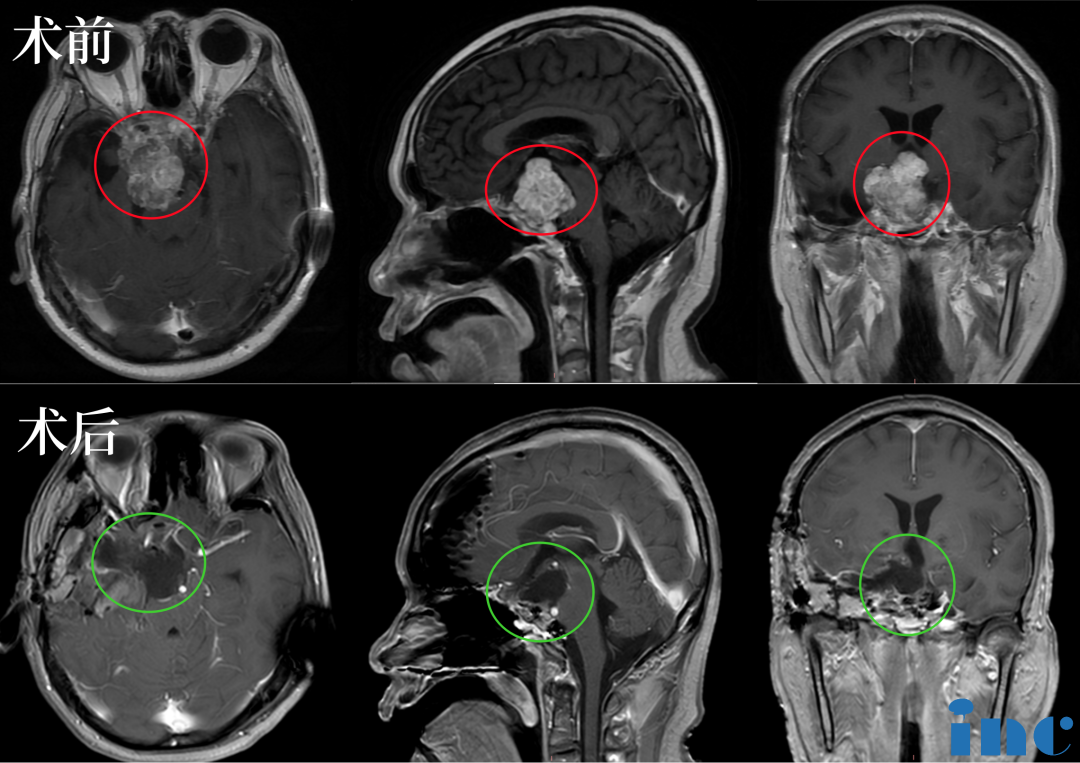

▲术前:肿瘤体大,广泛累及颅底结构,侵蚀斜坡、鞍内鞍上、海绵窦区,包裹右侧颈内动脉。肿瘤向上推挤视神经、视交叉,到达三脑室底部;向后上方推挤脑干和基底动脉,部分肿瘤边缘与脑干分界欠清。▲

“听闻福洛里希教授来华消息,我跟我儿子泪如泉涌,终于找到救星了。”这也是福洛里希教授在中国的一台技术示范教学手术,显微镜和内镜“双镜联合”,运用“筷子技术”,术后当晚核磁显示肿瘤已基本全切。苏先生术后神志清楚,四肢活动良好,无新增神经损伤和并发症。而经过这次成功的示范教学,福洛里希教授表示,后续双方应进一步加强合作交流,给更多脊索瘤患者提供国际前沿的规范化治疗。

▲术后:手术顺利,术中将鞍上鞍内、海绵窦区、三脑室肿瘤切除▲